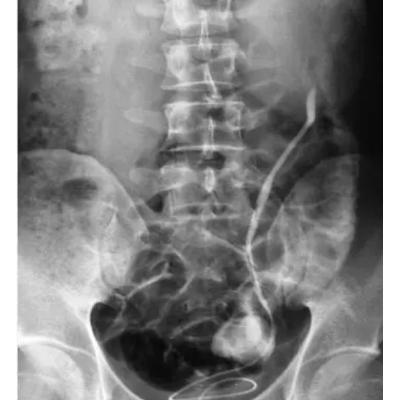

患者,男,17岁。诊断肾病综合征予泼尼松60㎎/d治疗,常规予护胃补钙等治疗。初起效果好,总蛋自、白蛋白、尿蛋白恢复正常。后减至泼尼松15㎎/d,症状反复患者未能配合治疗。予复治,患者不能有效配合治疗,有漏服药情况,激素治疗近1年,患者出现左股骨头缺血坏死。大家分析如何防范?及进一步治疗。

患者经停用激素后3个月,肾综症状再发,全身及双下肢重度水肿。经请外院专家会诊:股骨头缺血性坏死不宜行手术治疗,予环孢素口服治疗3周,效果欠佳,大家还有好办法吗?